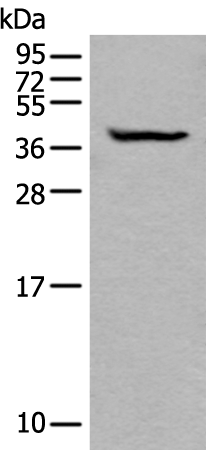

分类: 科研抗体货号: P08091别名: CALB应用: WB,IHC反应种属: Human, Mouse, Rat